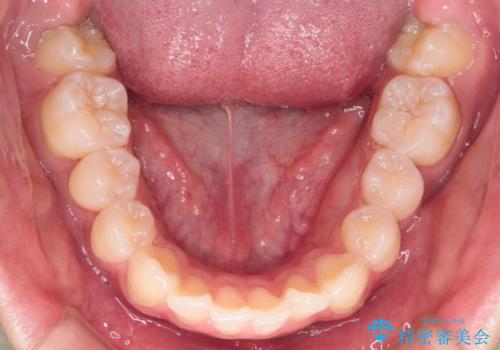

- 前歯が出ていることを主訴に来院されました。

臼歯関係が上顎前突傾向のため、上顎小臼歯を抜歯してインビザラインにて治療を行いました。

臼歯の咬合を作るために治療終盤ではゴムかけを行なっています。